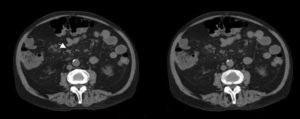

Case no. 2This patient was a 63-year-old man with systemic hypertension, renal failure, arthritis and a 9-year history of low back pain, with a diagnosis of spondyloarthritis. He had posterior uveitis and vitritis affecting right eye and had had 3 episodes of pancreatitis requiring hospital admission in the gastroenterology department. Computed tomography revealed nonspecific mesenteric lymph node enlargement (Fig. 1). Gastroscopy, during which a specimen was removed for biopsy, disclosed erosive disease involving the duodenal bulb. One month later, the patient was readmitted in the gastroenterology department with fever, diarrhea and abdominal pain. According to a duodenal biopsy (Fig. 2) that had been carried out during the earlier hospital stay, the diagnosis was Whipple's disease. Treatment was begun with ceftriaxone and imipenem, and included cefixime during the first 2 months. He was subsequently treated for 2 years with trimethoprim/sulfamethoxazole.